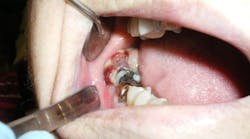

Removal of the lower third molars and the associated cystic lesions produced an expected histopathologic diagnosis of bilateral keratocystic odontogenic tumors. Because of the high suspicion of this diagnosis, surgery included aggressive removal of the lesions with peripheral ostectomy and treatment with Carnoy's solution.